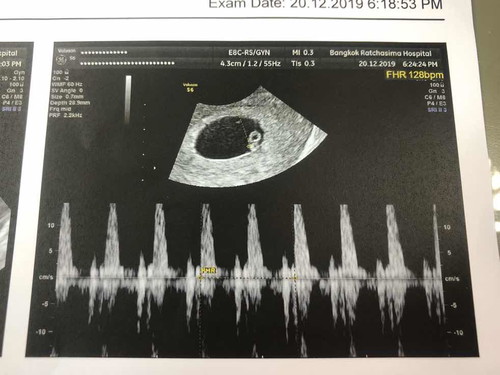

คุณหมอบอกว่าอัตราการเต้นของหัวใจช้า แต่ยังอยู่ในเกณฑ์ปกติ แอบเครียดนิดหน่อย แต่หนูต้องแข็งแรงๆ เข้มแข็งนะลูก แล้วเจอกันนะ ❤️ #6w4d

กำลังจะเป็นแม่